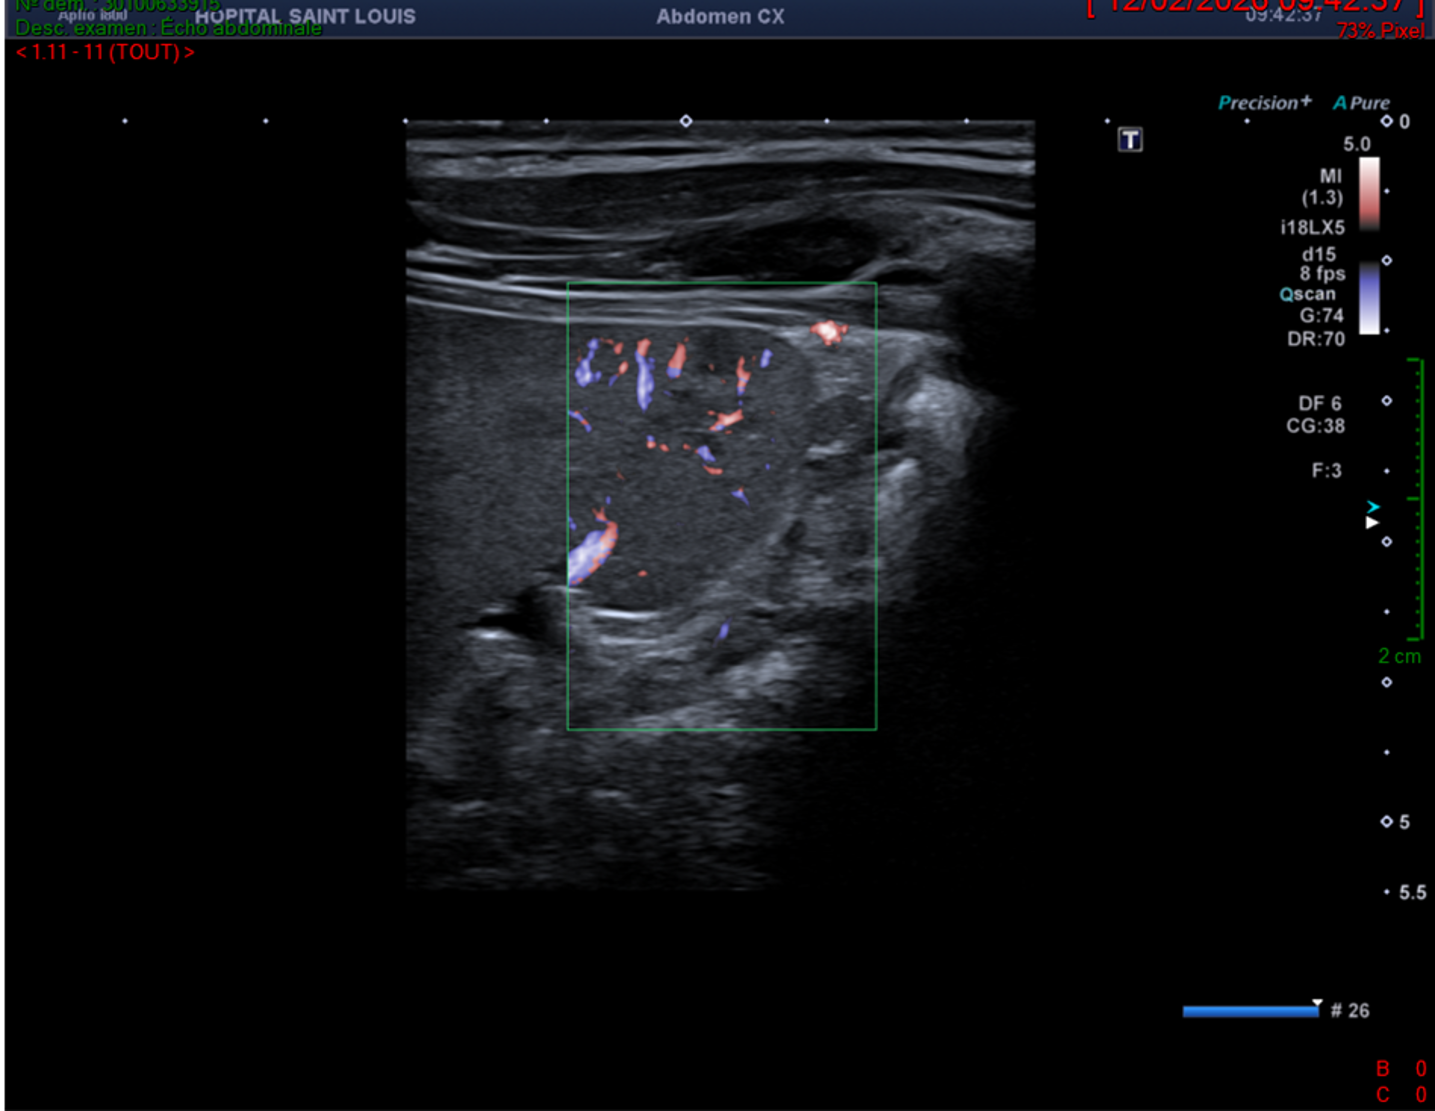

Rate étudiée avec une sonde linéaire de haute fréquence de 18MHz.

Rate étudiée avec une sonde linéaire de haute fréquence de 18MHz et Doppler de Haute Résolution (ADF).

La rate est le siège de plusieurs nodules hypoéchogènes, infracentimétriques, non vascularisés au Doppler de Haute Résolution..